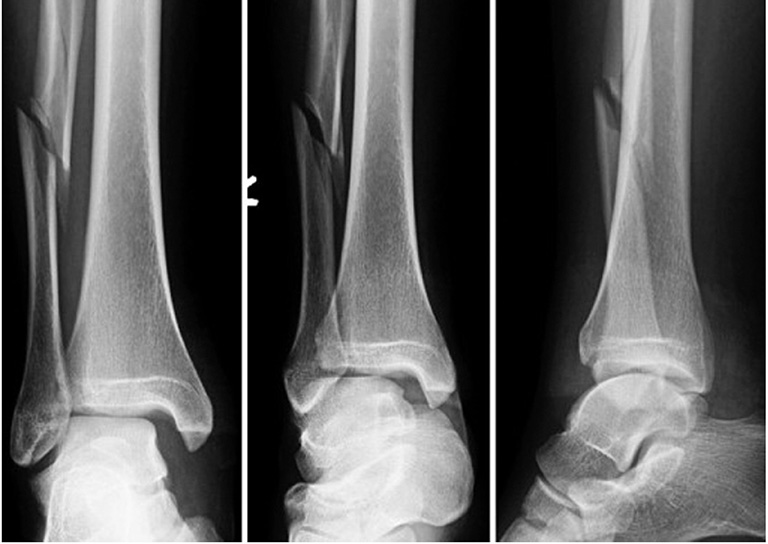

Gãy xương mác là tình trạng chấn thương nghiêm trọng thường xảy ra ở phần cẳng chân. Chấn thương này cần được xử lý và điều trị nhanh chóng để hạn chế những ảnh hưởng liên quan quá trình vận động về sau. Nhiều người lo lắng việc để xương mác lành như ban đầu sẽ gặp nhiều khó khăn. Vậy gãy xương mác bao lâu thì lành. Cùng Nhà thuốc Long Châu tìm hiểu bạn nhé!

Cẳng chân người được cấu tạo từ hai xương chính đó là xương chày và xương mác. Xương mác là phần xương có chiều dài và nhỏ nằm bên ngoài cẳng chân và bên ngoài của xương chày.

Xương có phần đầu dẹp và nhọn thẳng xuống dưới, chiếm khoảng 20% trọng lượng cơ thể tùy theo. Hai bộ phận xương này kết nối với nhau bằng chày mác và màng gian cốt.

Xương mác và xương chày được kết hợp và tạo cho chân có tử thế thẳng đứng. Hơn nữa còn giúp đình hình khớp gối và cổ chân một cách tốt nhất, giúp chân được linh hoạt hơn khi cử động.